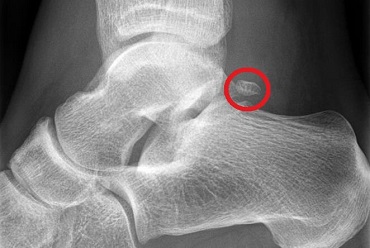

An Os Trigonum is a small, accessory bone that forms at the back of the foot behind the ankle joint.

However, sometimes it fails to join the talus and remains a separate piece of bone. It is usually small, less than one centimetre, and varies in shape from round to oval to triangular.